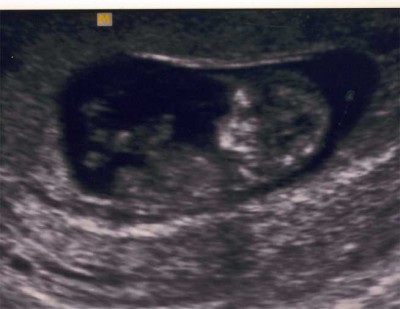

me : gestern war krümel-tv und es war suuuuuuuper!!!! der bauchzwerg war schon 4,1 cm groß und damit einen tag größer als er eigentlich ist

und er hat geturnt wie ein weltmeister... das war das erste mal, daß wir das gesehen haben und es war echt toll...da wurden beinchen geschwungen und arme haben gewunken und es wurde sich ständig um sich selbst gedreht, toll... papa hat 3d-us gemacht und der zwerg hat sich immer unerlaubt aus der meßebene entfernt

sooooo schöööööööööööööön... und dann ging der drucker nicht mehr und papa und mein schatzi haben dran rumgebaut und dann hatte ich den schallkopf ganz für mich und konnte dem zwerg ganz lange beim turnen zuschauen... grad schee wars...

ich stell euch mal die bilder hier rein...